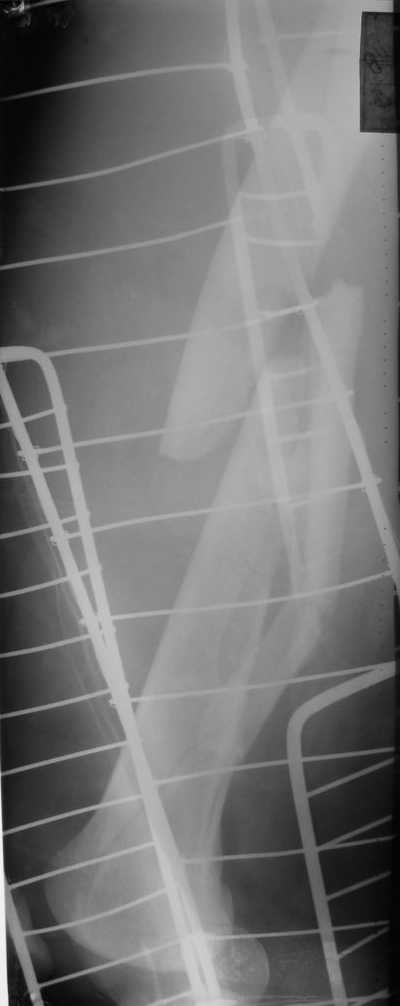

Уважаемые коллеги! Поступил пациент 46 лет после автоаварии от 3.01.

Лечился в ЦРБ. К нам поступил вчера. Имеется оскольчатый перелом диафиза

левого бедра, перелом медиального мыщелка, краевой перелом надколенника.

У нас, кроме того, выявили перелом шейки бедра. Перелом закрытый,

имеется рана в в/3 голени(ниже уровня бугристости б/берцовой кости)без

признаков инфицирования.